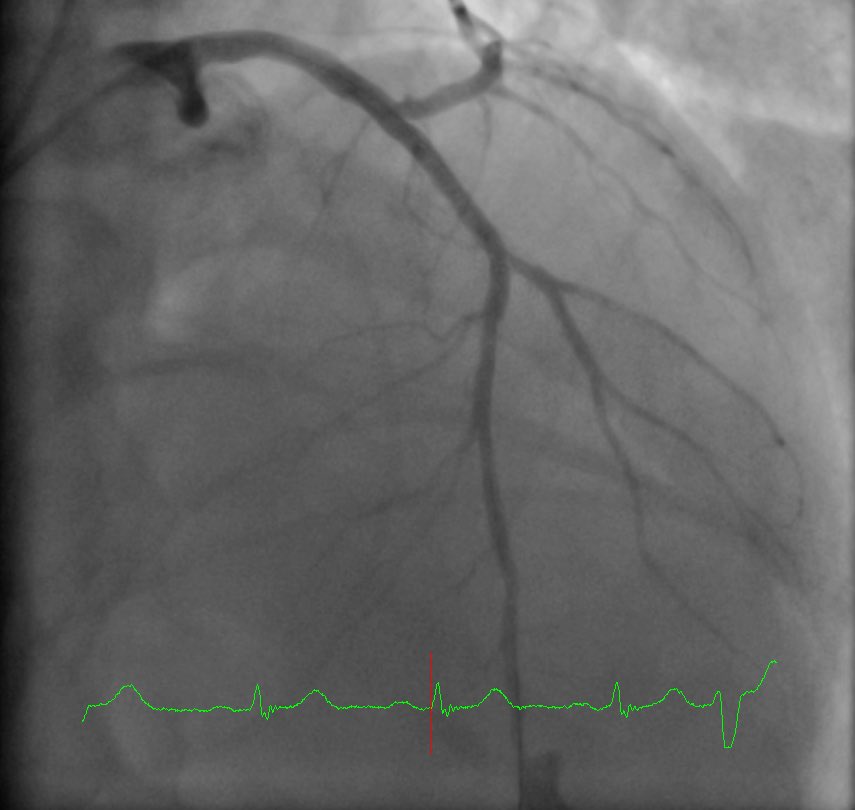

Ostial LCX is 99%, LM, LAD, Diag as you see. How do you tackle ⁦@ShariqShamimMD⁩ ⁦@Asaadakbarkhan

CheemaFACC's tweet image. Ostial LCX is 99%, LM, LAD, Diag as you see. How do you tackle ⁦@ShariqShamimMD⁩ ⁦@Asaadakbarkhan⁩